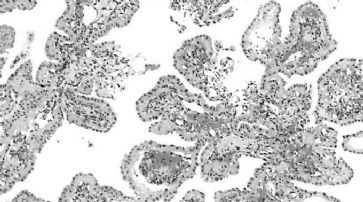

Nach aussen sichtbar ist vor allem das Übergewicht, doch im Blut finden sich zu viele Fette, Cholesterin, Zucker, Insulin, IGF-1 und Aminosäuren, die eine anabole Mast auslösen und ideale Voraussetzungen für gut- und bösartiges Zellwachstum schaffen. Auch die Ausschüttung von Hormonen wird so stimuliert. In der Prostata führt dies zunächst zu einer gutartigen Prostatahyperplasie (BPH).

Gesunde Ernährung und Bewegung ist der Schlüssel. /

Die BPH resultiert in einer vermehrten Anfälligkeit der Prostata für Entzündungen oder verstärkt diese in Form eines Teufelskreises. Denn Entzündungsprozesse fördern wiederum das Wachstum der Prostata und die BPH.

Die Stoffwechselprozesse bei einer chronischen Prostataentzündung (Prostatitis) fördern schliesslich, insbesondere durch den dauerhaft erhöhten oxidativen und nitrosativen Stress, die Entstehung von Prostatakrebs. Dazu tragen auch Beschwerden beim Wasserlassen und Stuhlgang bei, die zum vermehrten Ausüben von Druck führen können, was das Eindringen von Keimen in die Prostata begünstigt.